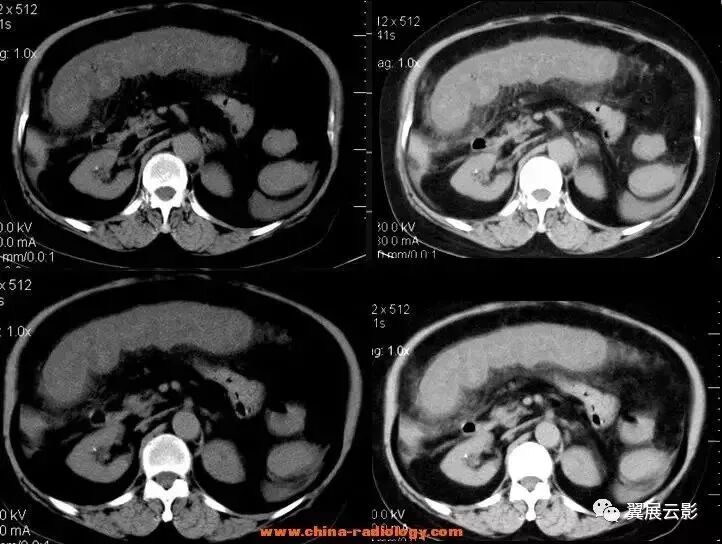

以下两例均是胆管癌,可以看出有明显的肝包膜内陷: